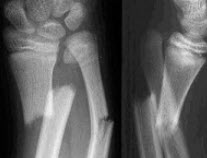

161、单项选择题

男,7岁,肘部外伤,根据所示图像,最可能的诊断是()

A.尺骨中上段骨折

B.桡骨小头脱位

C.孟氏骨折

D.盖氏骨折

E.以上均不正确